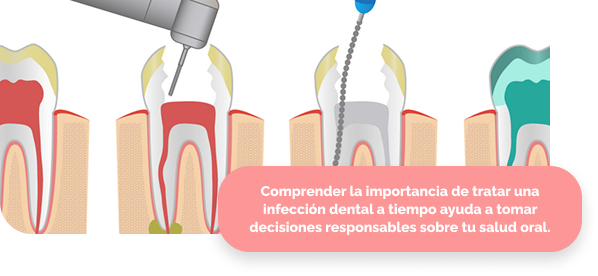

🦠 ¿Por qué es importante la endodoncia?

La endodoncia es fundamental cuando el nervio del diente se encuentra inflamado o infectado. Tratar el problema a tiempo evita la extracción dental y previene complicaciones mayores que pueden afectar la salud bucal general.

Tratamiento de conducto

Eliminación del tejido infectado del interior del diente, limpieza profunda y sellado de los conductos radiculares para evitar futuras infecciones.